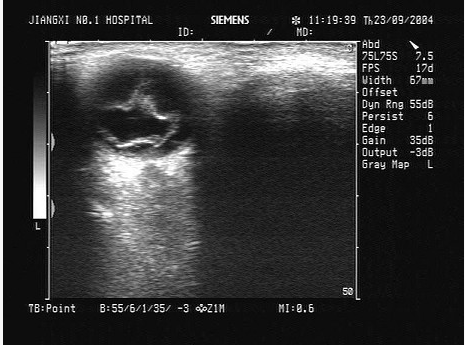

4、单项选择题

某近视患者,眼部碰伤后,视物不清。眼部超声如图,最可能的诊断为()。

A.视网膜完全脱离

B.视网膜局限性脱离

C.眼内异物

D.玻璃体血块

E.以上均不对